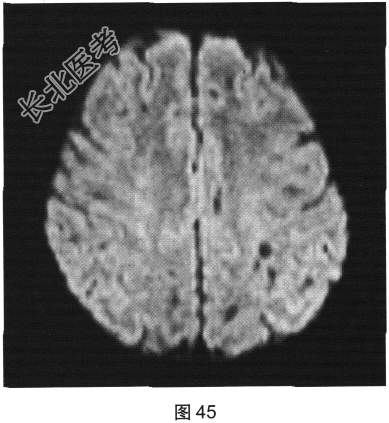

- 多项选择题2.[提示]患者行FLAIR、DWI及增强扫描,见图45~图54。该患者MRI影像的主要阳性表现有( )

D、病灶呈长T1、长T2信号,FLAIR为低信号,DWI为高信号,ADC为低信号

E、病灶呈长T1、长T2信号,FLAIR为低信号,DWI为低信号,ADC为高信号

F、病灶呈长T1、长T2信号,FLAIR为稍高信号,DWI为低信号,ADC为高信号